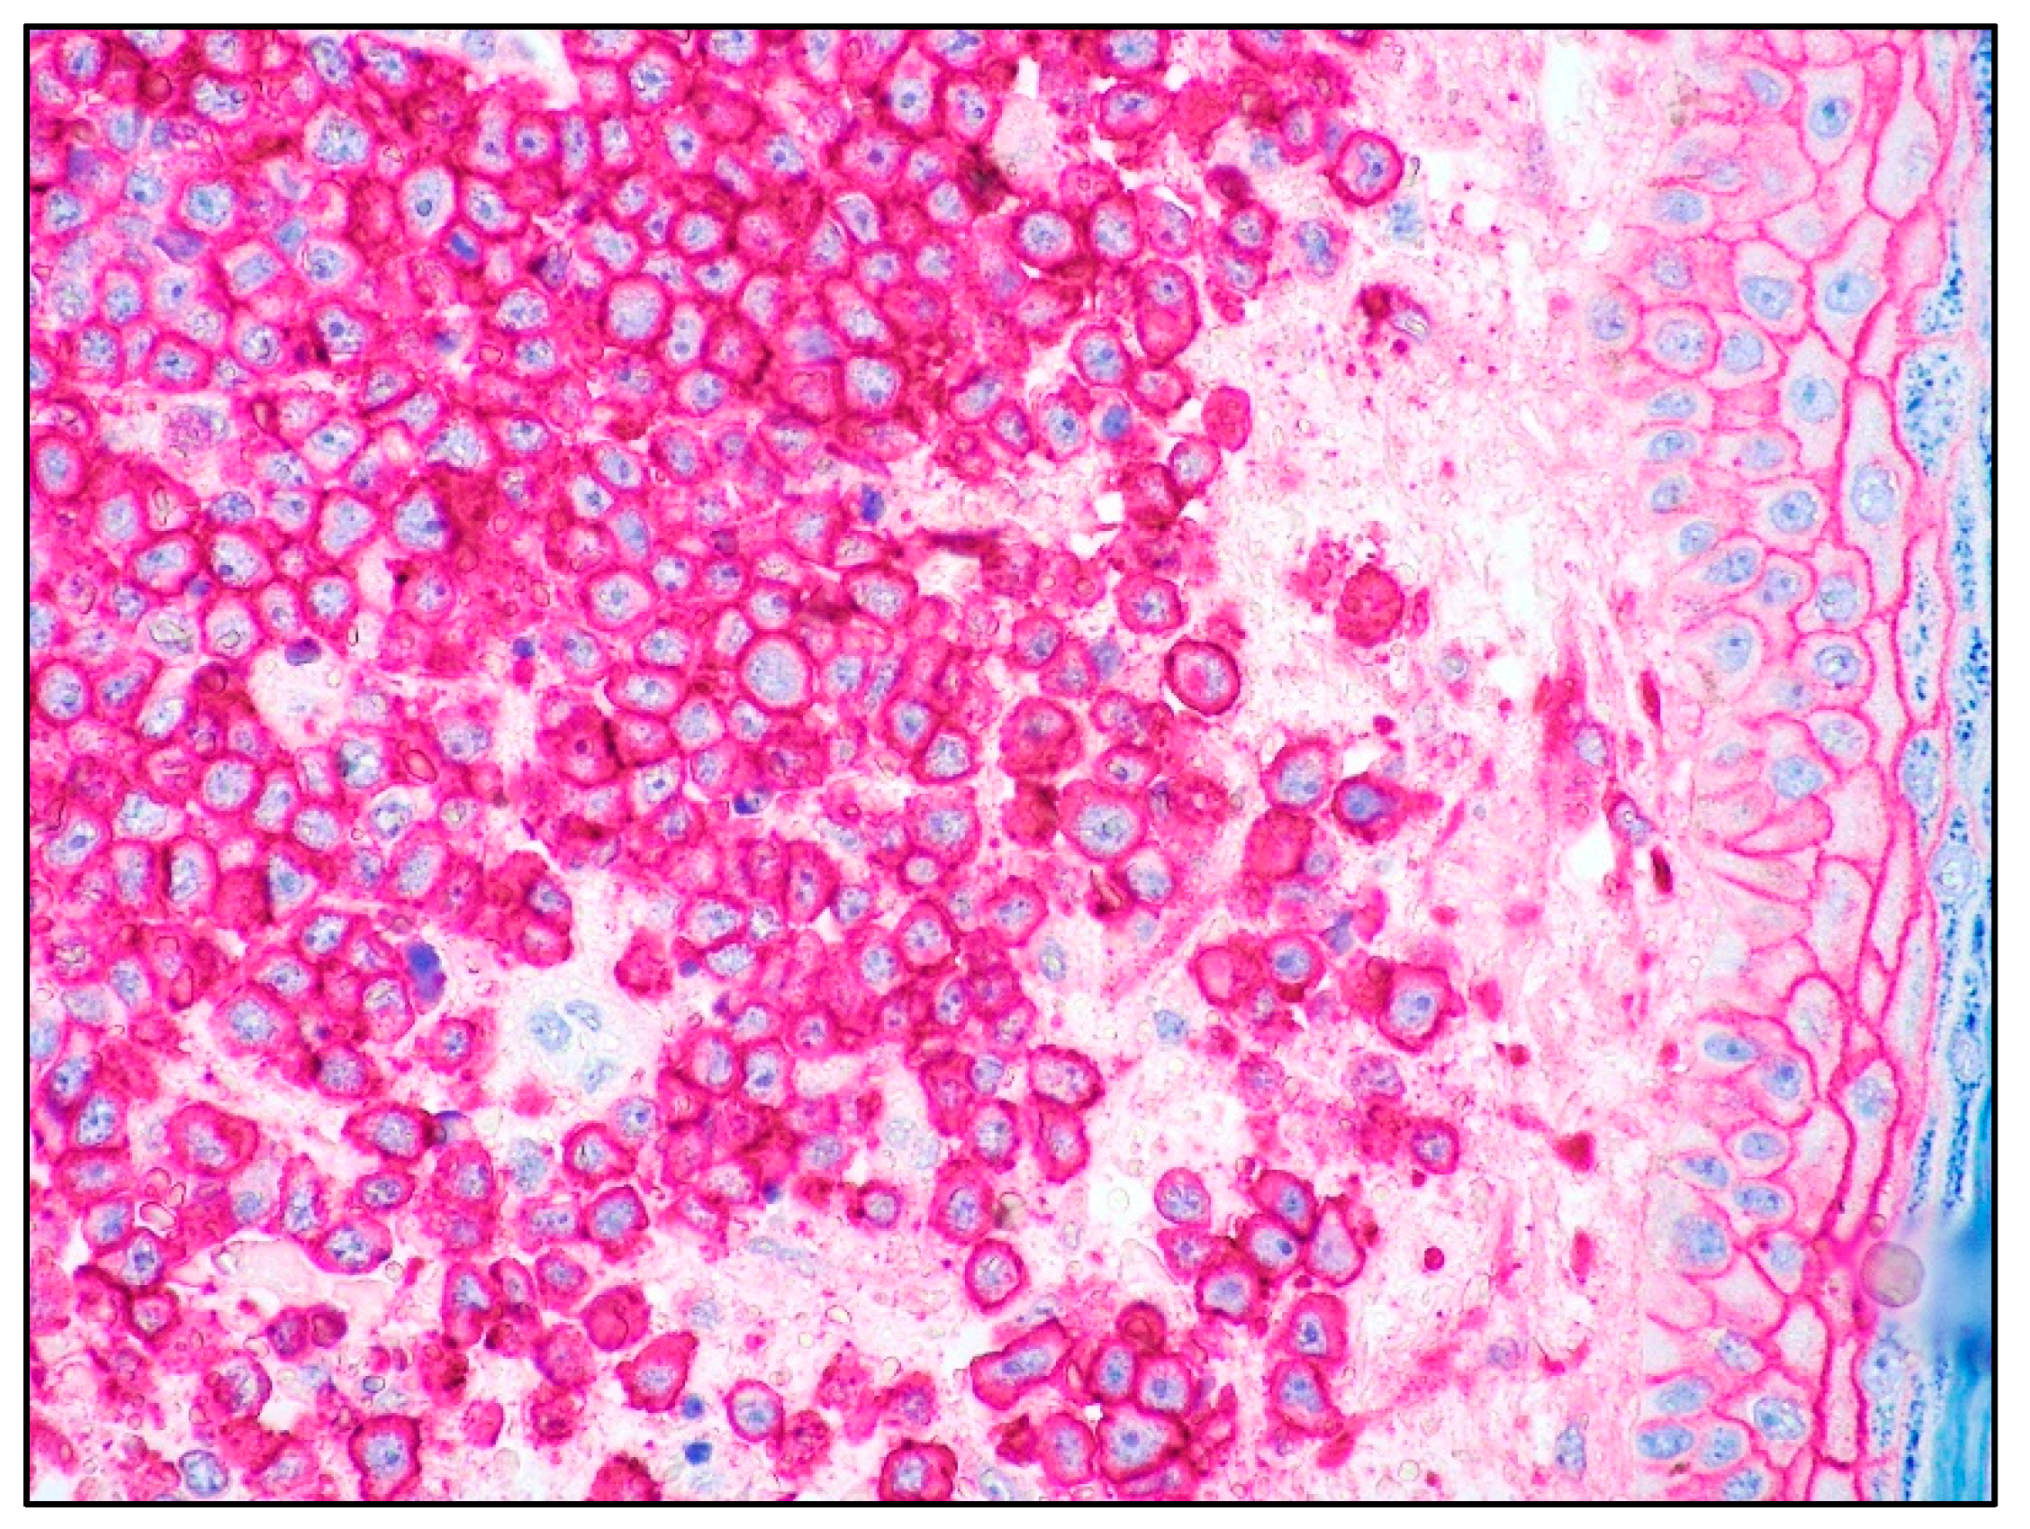

4. Blastoid MCL: General Features

5. MCL and Skin Involvement